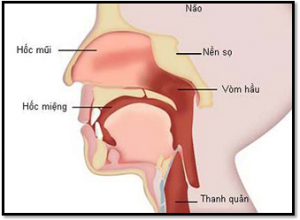

Yếu tố bất ngờ gây ung thư vòm hòng

So với trước đây, ung thư vòm họng trở nên phổ biến hơn, đây là [...]